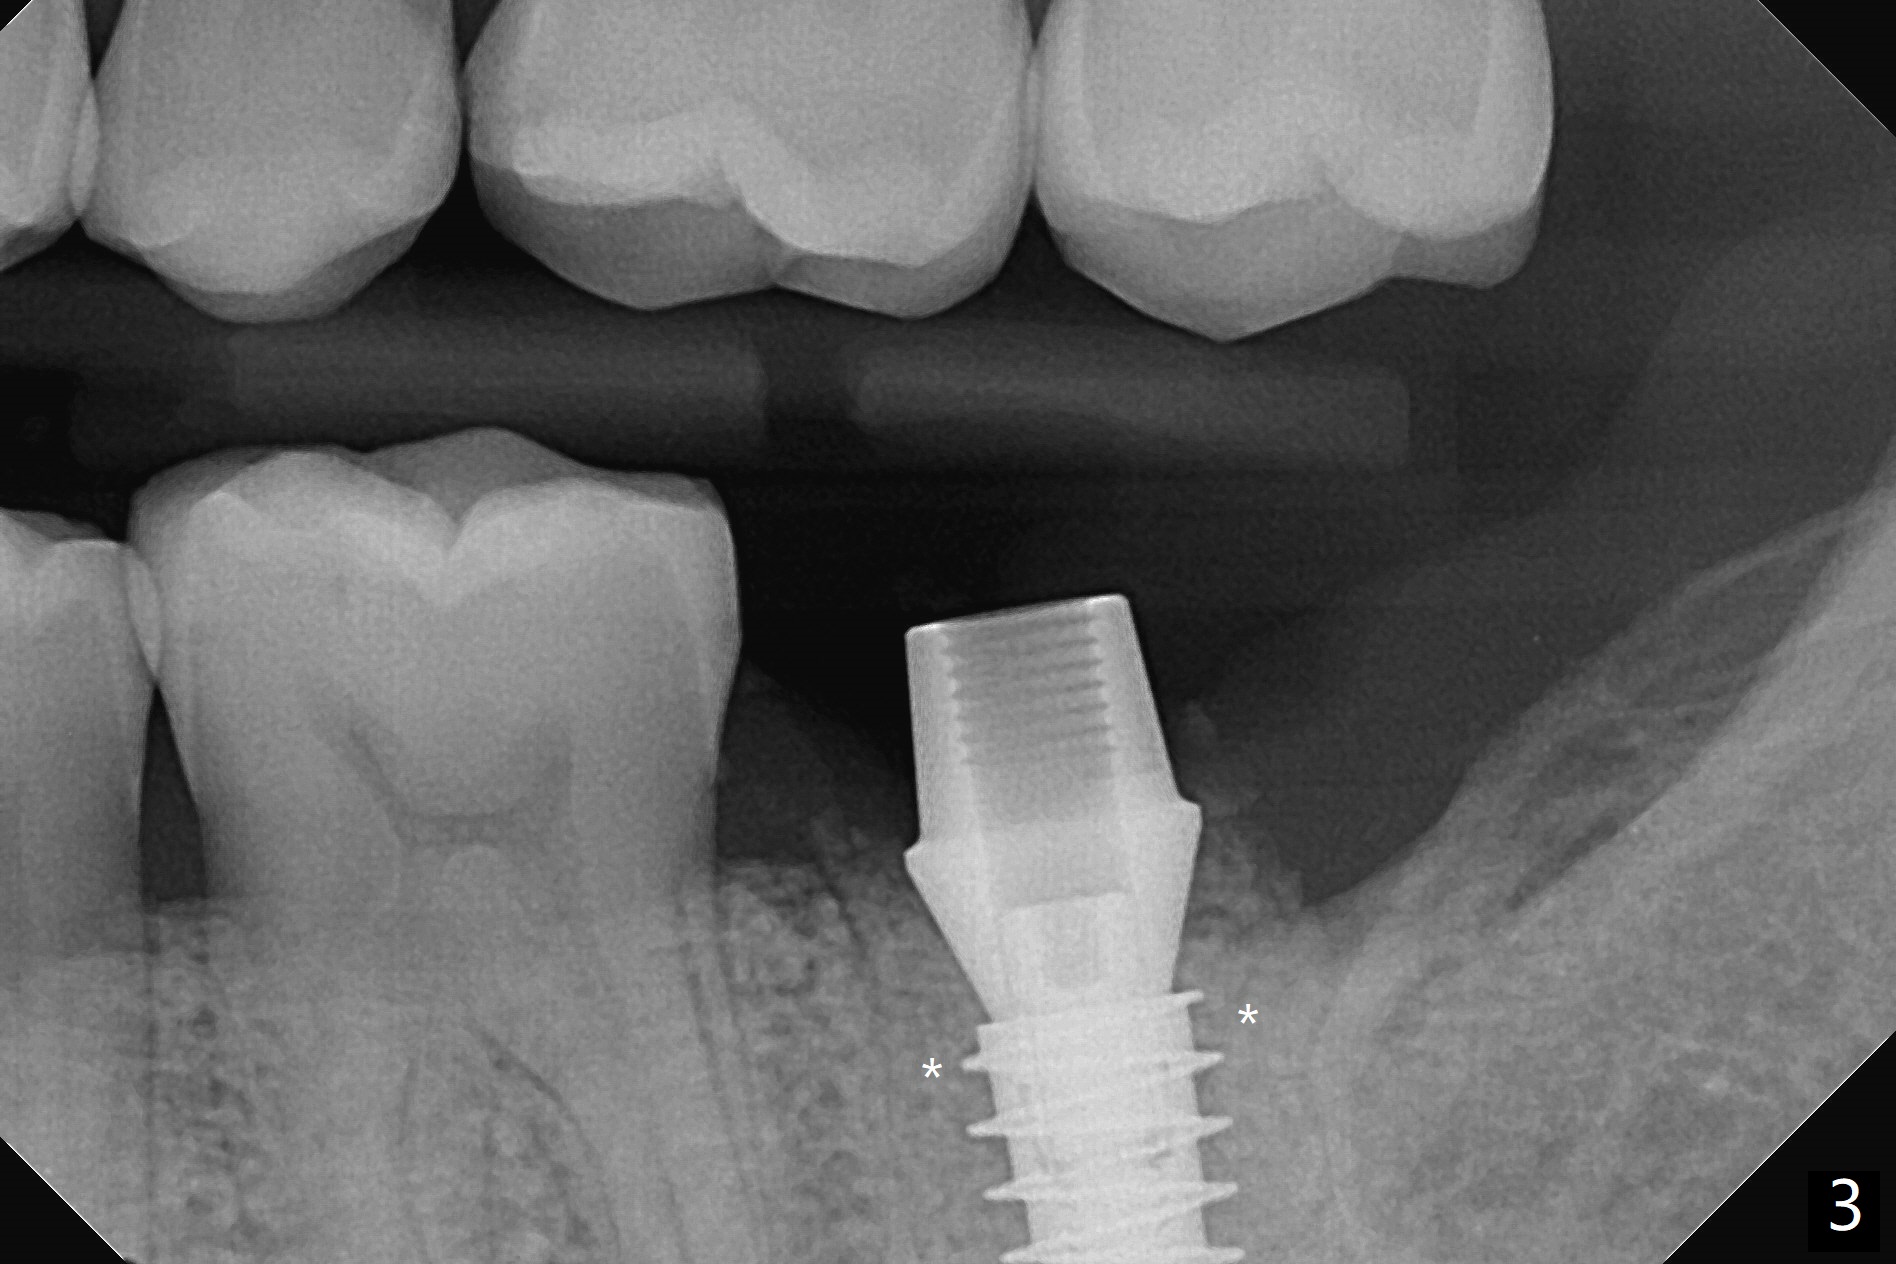

18号牙远中龈下龋齿,在导板指引下,使用4.0x8.5毫米钻头后,钻洞建立在中隔(图一:S)近中舌侧,5.0x9毫米植体似乎还没有超出牙槽窝轮廓(图二),已经取得35Ncm扭力。放置基台后,放入足够粘性骨粉(图三:*),然后制作临时牙冠,结合PRF,固定骨粉。由于植体没有接触牙槽嵴,那里骨质吸收将是轻微的,而骨质再生显著。